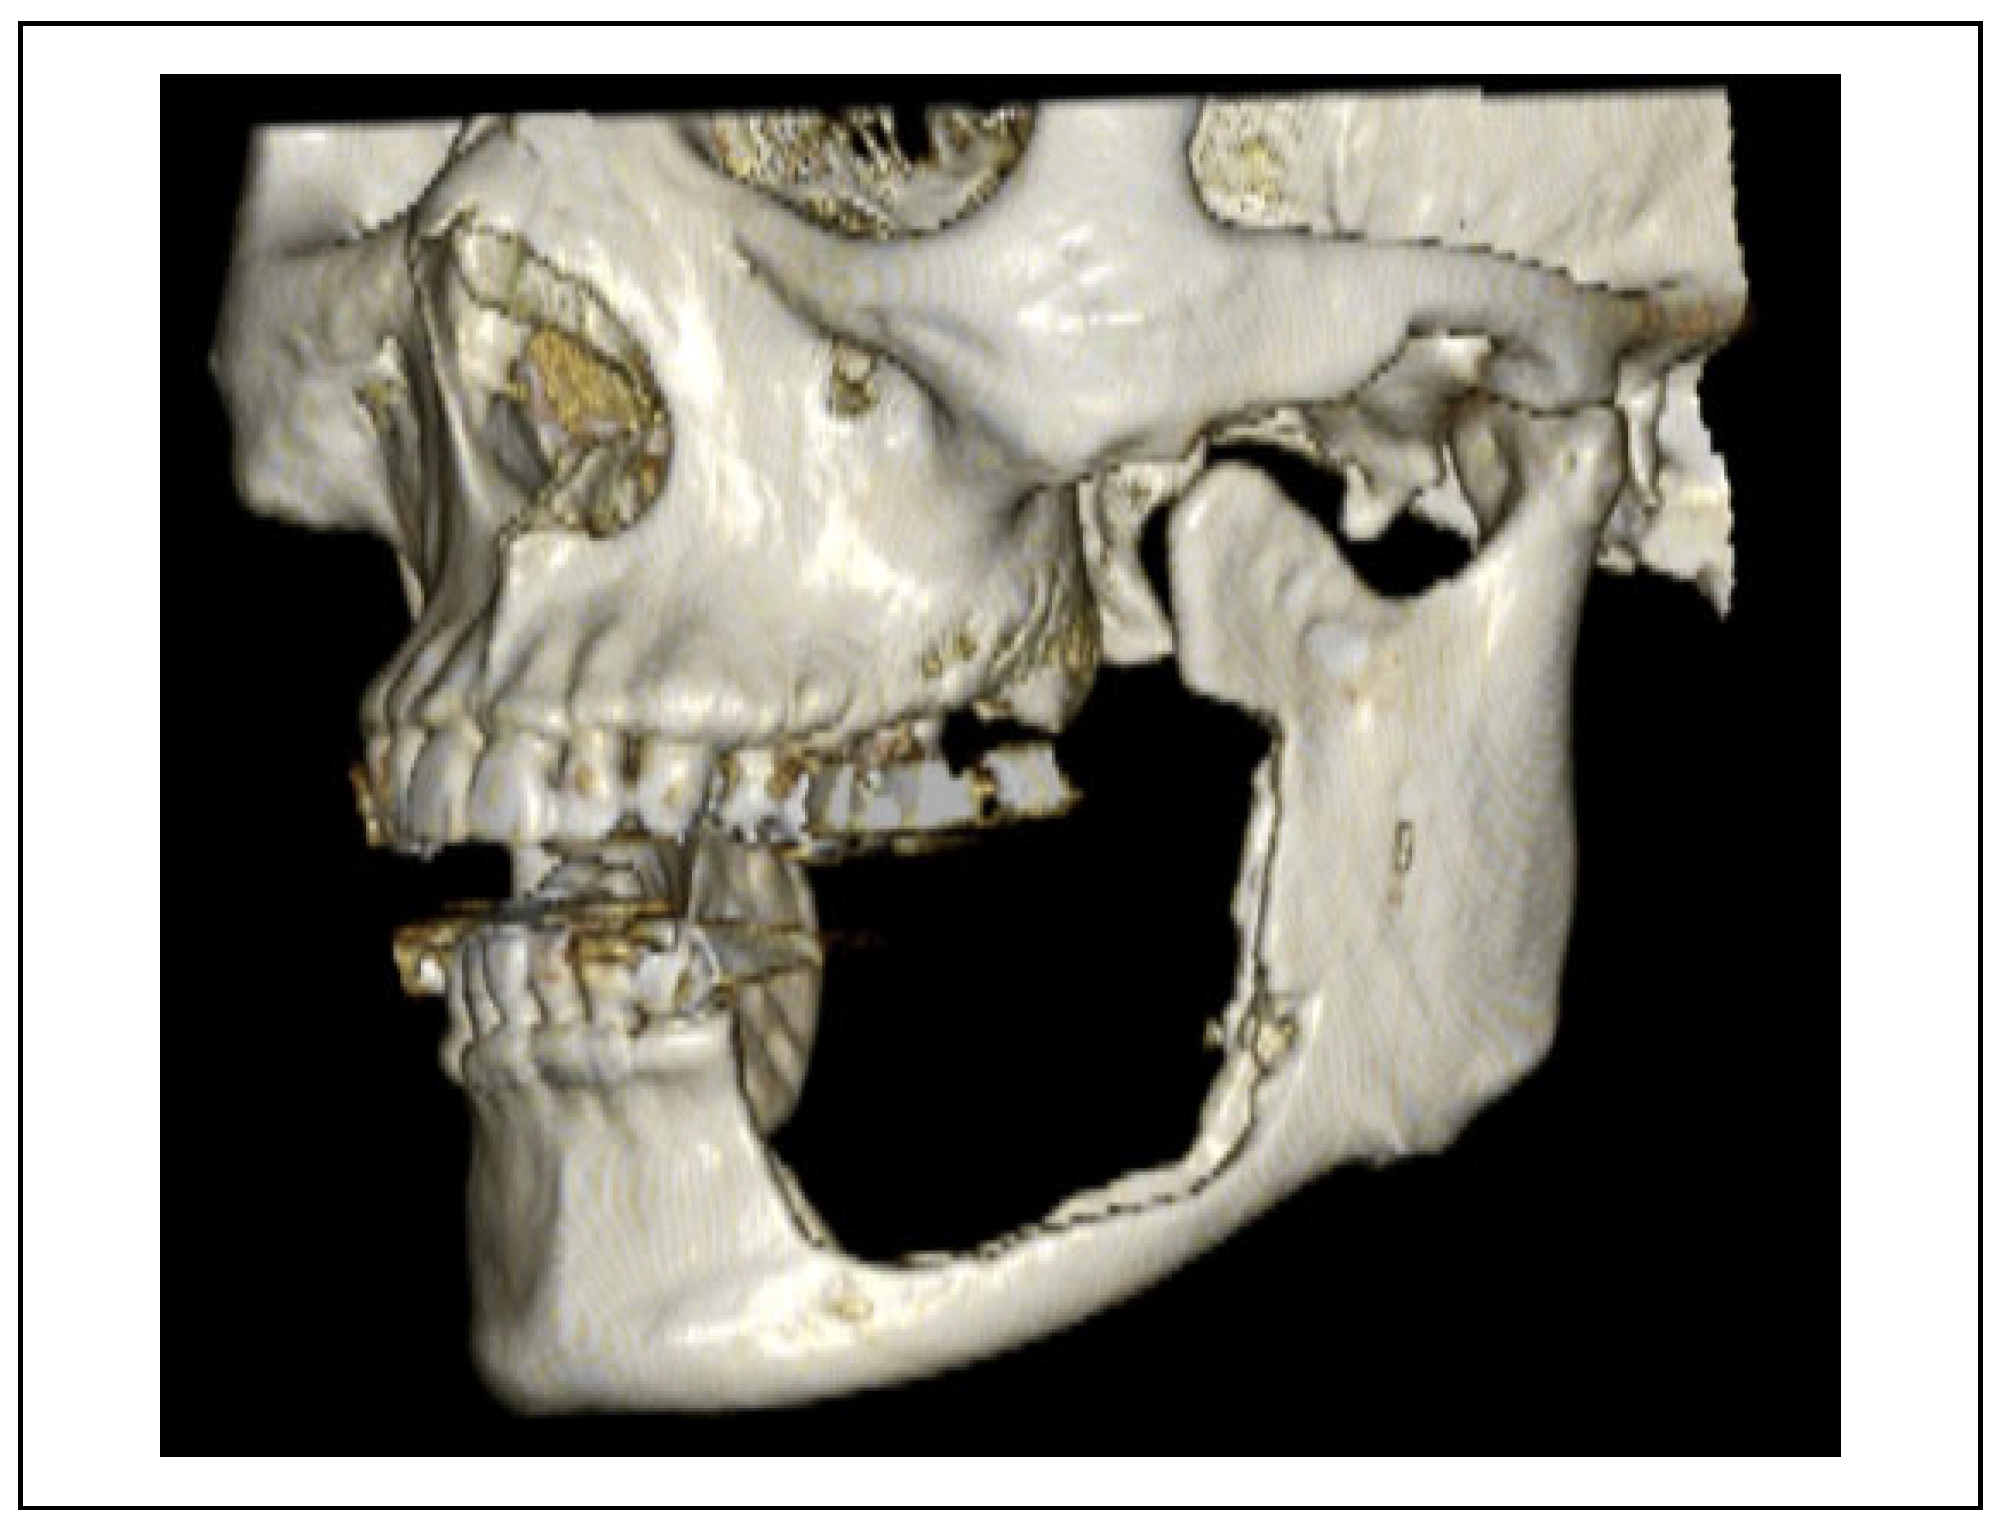

Case Presentation

Surgical Procedure